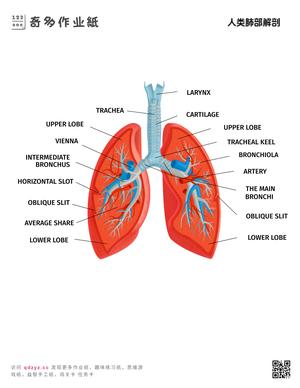

奇多作业纸生活常识系列提供幼儿通识教育资源,涵盖天气与季节认知、人体部位图解、交通安全常识、动植物百科、日常卫生习惯等核心主题。内容设计参照《3-6岁儿童学习与发展指南》科学领域目标,通过图片认知、分类游戏和问答练习三种形式实现多维度学习。常识教育是幼儿建立世界认知框架的基础环节,也是幼小衔接面试的常考内容。所有资源下载打印,适合3-7岁儿童使用。

- 掌握基本身体部位名称和功能

包括:交通安全规则(红灯停绿灯行)、卫生习惯(饭前洗手)、四季变化特征、基本身体部位名称、常见动植物辨认、简单的天气现象识别等。

通过图片闪卡、问答游戏和场景模拟三种方式效果最佳。例如用天气卡片认识晴天、雨天;用人体图谱学习身体部位;用交通标志卡开展安全教育。